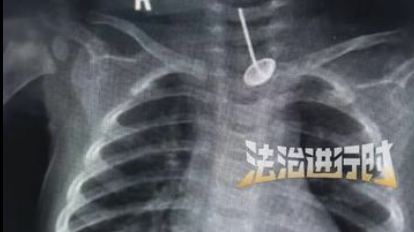

婴儿误食鞭炮嘴巴被炸伤 送医后发现食管内还有一颗钉子 经救治化险为夷 目前恢复良好